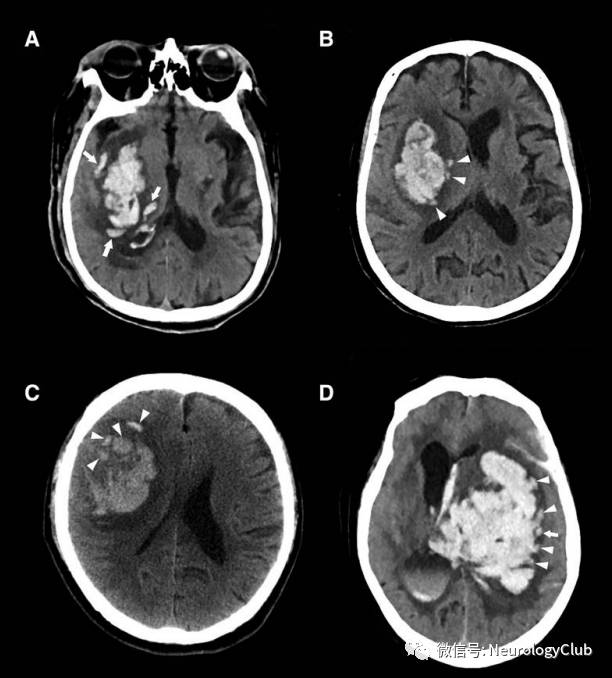

混合征

2015年,李琦等提出CT平扫混合征,并将其定义为同一血肿内混合存在相对低密度区与相邻高密度区的现象,且需满足:(1)低密度区与高密度区之间有明显可被肉眼识别的分界;(2)血肿中2个密度区CT值至少相差18HU;(3)相对低密度区未被高密度区完全包裹。当血液凝固时,血肿在CT上表现为高密度;存在活动性出血时,血肿较血块凝缩更倾向于低密度,不同出血时间的血液混合导致混合征的出现,血肿再次出血进一步导致血肿扩大发生。合征预测ICH患者血肿扩大的敏感性、特异性、阳性及阴性预测值分别为39.3%、95.5%、82.7%和74.1%,比点征具有更高的特异性。首次CT混合征阳性的ICH患者血肿体积明显>阴性者,并且血肿更易扩大,因此混合征可作为血肿扩大的独立预测因素。最近研究发现,脑出血上可见混合征患者预后较差。

(图3:基底节和脑叶出血的混合征)

(图4:脑出血混合征)